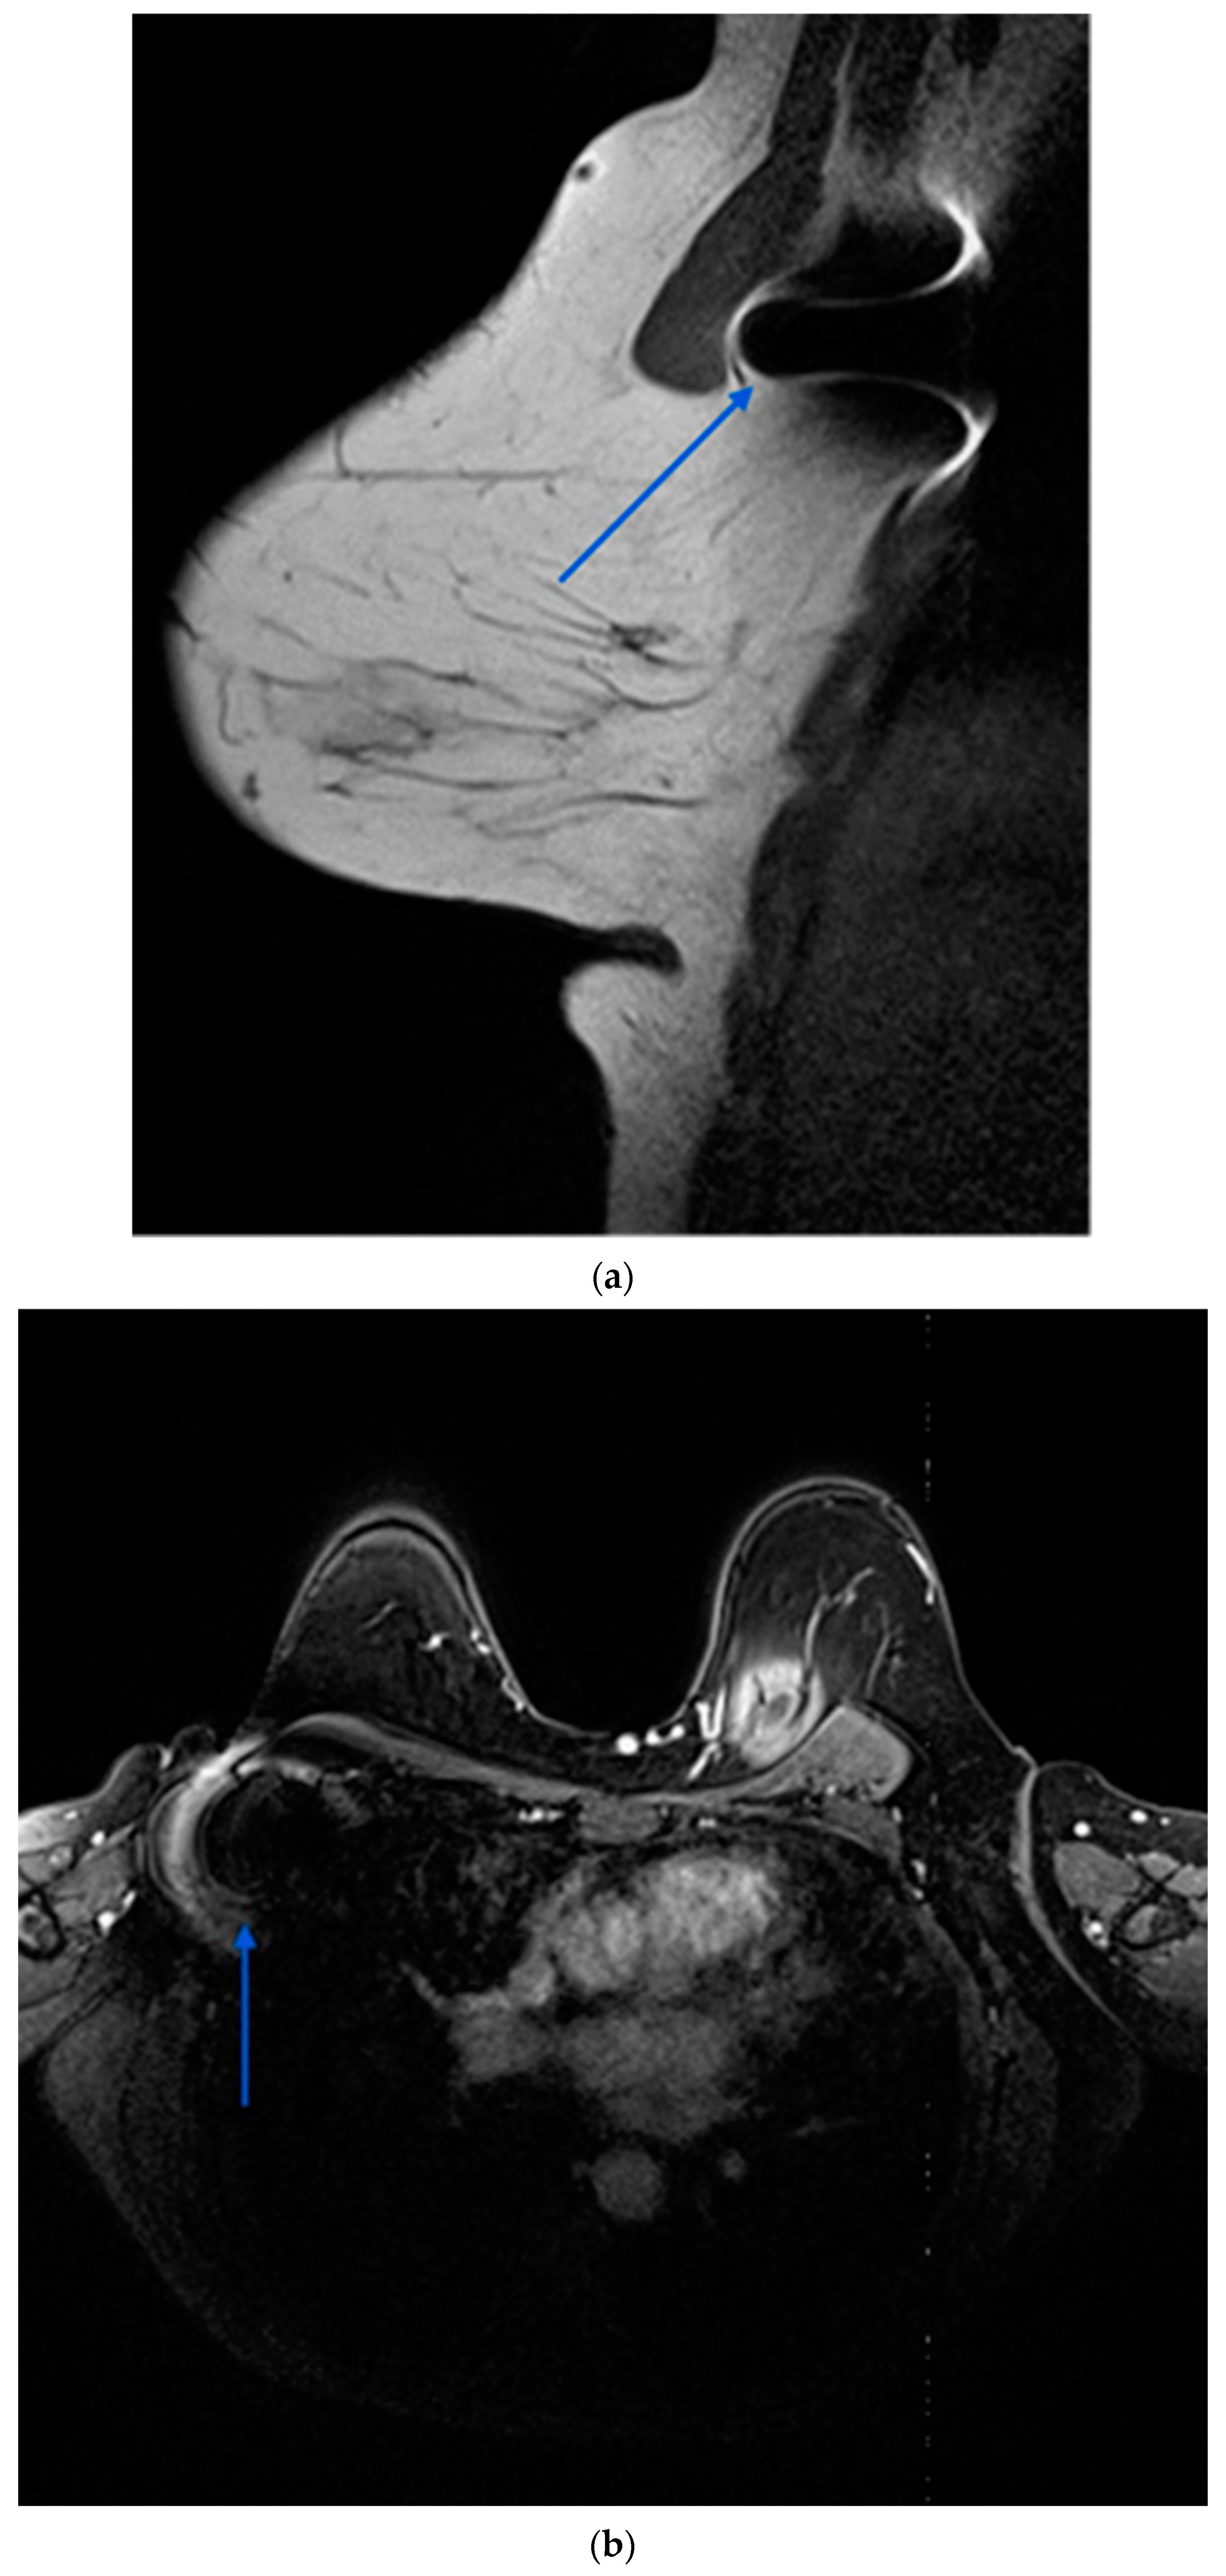

4.2. Comparison of Wireless Technologies for Localisation

Several localisation technologies, including RSL, magnetic seeds (Magseed®), radio-frequency identification (RFID) tags, and SAVI SCOUT, offer advantages and limitations. Magseed®, a non-radioactive wireless marker, demonstrates high localisation rates and can be deployed at the time of biopsy, facilitating streamlined surgical procedures. However, it entails higher costs and may interfere with MRI interpretation due to the generation of significant void signals up to 4 cm (Figure 4) [5,24].

SAVI SCOUT, another non-radioactive wireless option, provides accurate localisation but is larger than Magseed® and lacks flexibility in marker adjustment post deployment [28].

A prominent limitation of the Magseed® system would be the requirement to remove all metal instruments from the surgical field during the use of the Sentimag probe. Furthermore, the ferromagnetic seeds interfere with MRI creating significant artefacts that can compromise the assessment of response to NST in both the axilla and the lateral aspect of the breast [29,30]. Additional drawbacks of this technology involve the necessity for frequent recalibration of the Sentimag due to interference from paramagnetic equipment, as well as its limited depth for accurate detection, which extends only up to 30 mm.

Figure 4. Contrast enhanced MRI after completion of NST demonstrating ferromagnetic artefact (blue arrows) generated by a magnetic seed previously placed in a right pathological axillary lymph node. (a): sagittal view; (b): axial view.